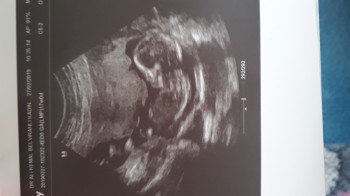

Şekerim ve tansiyonum var bugünde kontrolüm var demistim sabah kızlar çok şükür bebegim gayet iyi hiç bi sıkıntı yok cinsiyetinide öğrendim sonunda Allah nasip ederse kizim olacak :) Rabbim tüm dua bekleyenlere yardımcı olsun inşaallah

Gebelik haftası 17

Amin insaallah canim .Doktorum gösteriyor herseyini canım zaten ki çok da belli bunda sağ taraftaki kafası